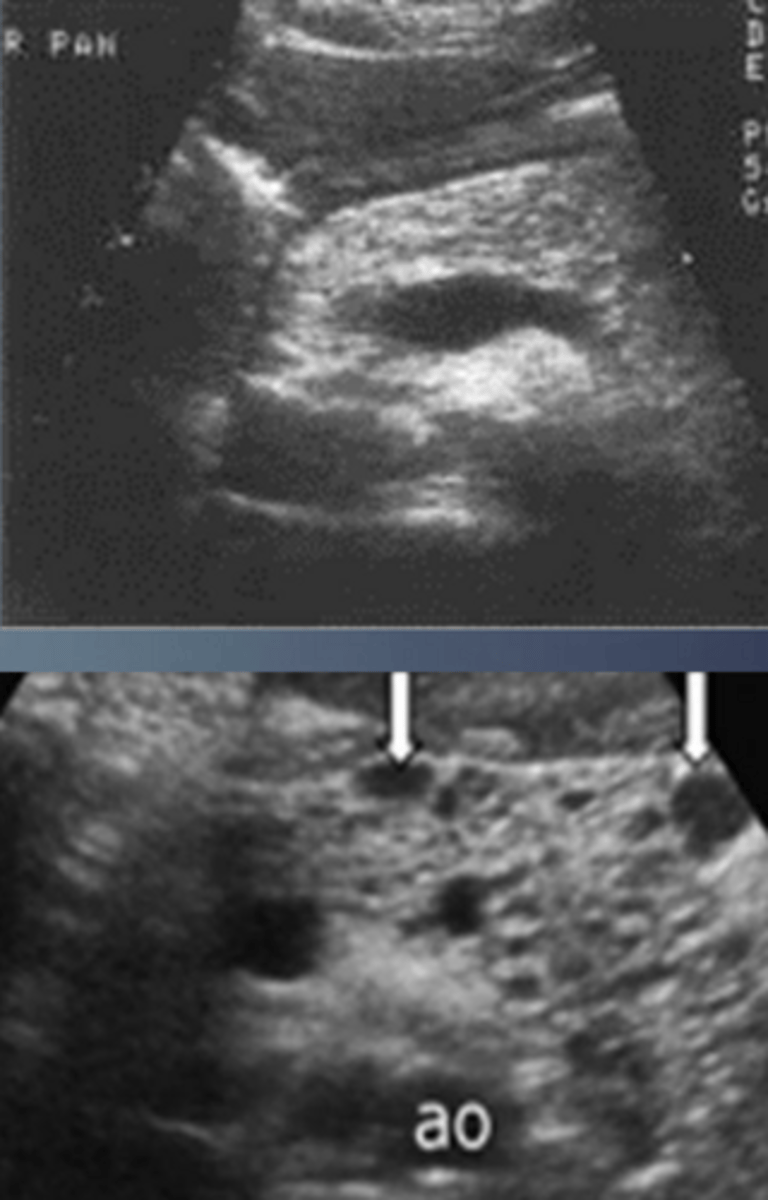

Cystic Fibrosis Sonographic Appearance

-generally hyperechoic due to microcystic changes and increased fatty and fibrotic infiltration

-inhomogenous

-cannot compare echo texture of liver to pancreas (either organ may display abnormal echo texture)

Cystic Fibrosis

Biliary/Liver Sonographic Appearance

-biliary stasis

-focal biliary cirrhosis/fibrosis is common as pt ages

-portal HTN

-cannot compare echo texture of liver to pancreas (either organ may display abnml echo texture)

Liver/Biliary Tract

GI Sonographic Appearance

-meconium ileus in neonates

-chronic obstructions (inflammatory bowel processes)

-thickened irregular folds = donut sign

-redundant GI tract and unavailable scan window thru LT lobe of liver

-non visualized GB or GB filled w/ thick echogenic bile (sludge)